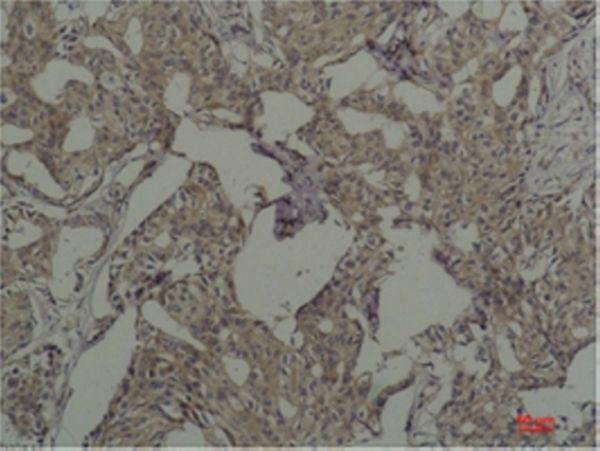

Immunohistochemical analysis of paraffin-embedded Human Breast Caricnoma using c-FosMouse mAb diluted at 1:200.